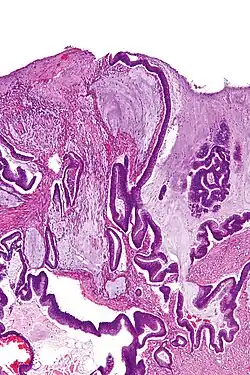

Micrograph of a mucinous adenocarcinoma of the colon. H&E stain. | |

A mucinous neoplasm (also called colloid neoplasm) is an abnormal and excessive growth of tissue (neoplasia) with associated mucin (a fluid that sometimes resembles thyroid colloid). It arises from epithelial cells that line certain internal organs and skin, and produce mucin (the main component of mucus). A malignant mucinous neoplasm is called a mucinous carcinoma. For example, for ovarian mucinous tumors, approximately 75% are benign, 10% are borderline and 15% are malignant.